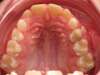

Avant

Résultats

Après